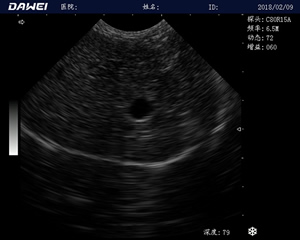

MT15獸用B超機適用探頭

牛羊馬豬犬貓及多種家禽、實驗動物、野生動物、及部分水生動物

中小動物的肝、膽,脾、腎、膀胱、子宮、妊娠等各組織器官的檢查和病變的診斷